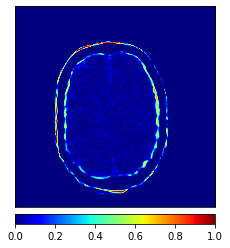

In this paper, we propose a bidirectional learning model, known as dual contrast cycleGAN (DC-cycleGAN), for medical image synthesis from unpaired data. Specifically, a dual contrast (DC) loss is formulated that leverages the advantage of samples from the source domain as negative samples to indirectly build constraints between real source and synthetic images via discriminators, and synthesize images more related to the target domain by enforcing the synthetic images to fall far away from the source domain. In addition, structural similarity index (SSIM) [35] and cross-entropy (CE) [48] are integrated into the DC-cycleGAN structure to avoid disappearing gradient information that is caused by a mean absolute error (MAE) and synthesizing irrelevant images. SSIM considers luminance [35] and CE converges fast as its back-propagation error is less than MSE [28]. As can be seen in Figs. 1 and 2, using SSIM and CE with dual contrast can generate more clear and accurate MR images as compared with that of MAE and MSE, and SSIM and CE without dual contrast loss. Although both SSIM and CE with dual contrast and without dual contrast generate similar CT images, SSIM and CE with dual contrast quantitatively generate better images as shown in Table 4. The experimental results indicate that DC-cycleGAN is able to consider more complex features such as structure in synthesizing images and produce remarkable results as compared with other state-of-the-art methods reported in the literature.

Tables 3 and 4 show the results of MR and CT synthesis, respectively. As can be seen, all components play vital role in both tables. SSIM & CE (w) performs significantly better than other losses in synthesizing MR images. This also can be seen visually in Fig. 1. In contrast, SSIM&CE (w) performs slightly better than SSIM&CE (wo) in synthesizing CT images, both generate more or less similar CT images (see Table 4).